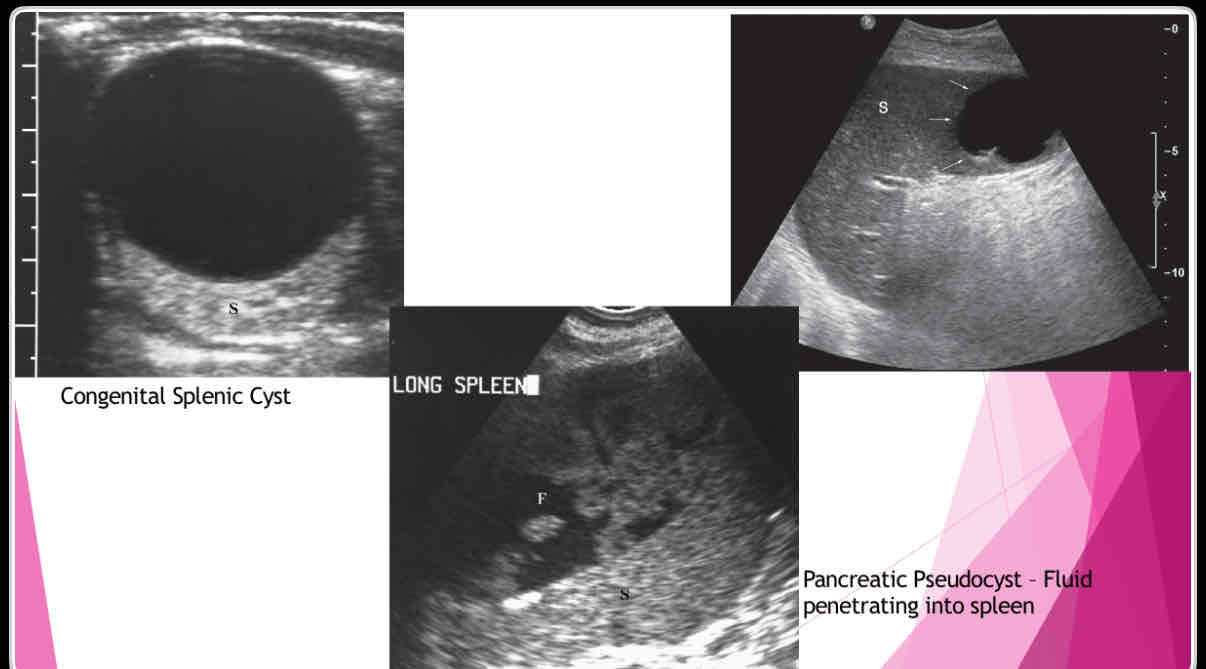

What does the following describe?

•Anechoic, well-defined walls, enhanced sound transmission

•Sharply demarcated wall, multilocular internal structure representing daughter cyst, mural calcifications

•Large cysts, dense, clearly defined walls May not have well-defined wall, mural calcifications Single or multiple simple cysts

splenic cysts

What are the different types of splenic cysts?

•Can be Congenital

•Can also be Acquired

• Echinococcal (hydatid)

•Epidermoid or epithelial

•Posttraumatic or postinflammatory pseudocysts

What does the following describe?

•True cysts lined by squamous epithelium

•Typically solitary, 10 cm

•Wall may be calcified and internal contents echogenic

Epidermoid or epithelial

What does the following describe?

•Polycystic kidney disease lymphangioma,

•extension of pancreatic pseudocyst

-Erode into spleen due to proximity

-May weaken vessels causing pseudoaneurysms and bleeding into pseudocyst

Posttraumatic or postinflammatory pseudocysts